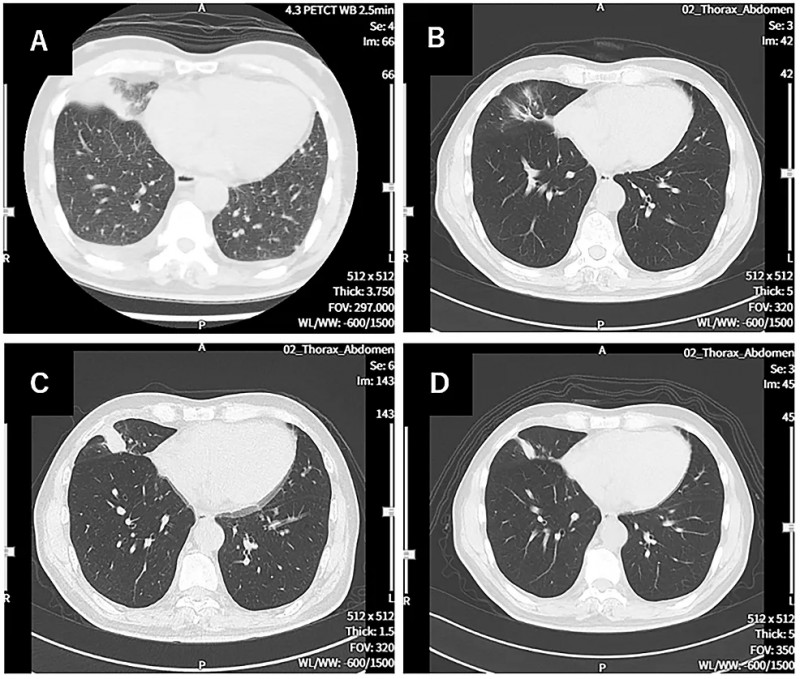

此外,PET-CT评估显示,治疗前患者除右下肺原发肿瘤外,还伴双侧肺内、骨及肝多发性转移;治疗479天后复查,仅残留右肺2个直径1.0cm病灶、肝脏1个直径1.7cm小转移灶,其余部位未发现新增转移灶(详见下图)。最终患者临床状态良好,体能状态(PS)评分为1分,可正常生活。

▲图源“Cureus”,版权归作者所有,如无意中侵犯了知识产权,请联系我们删除